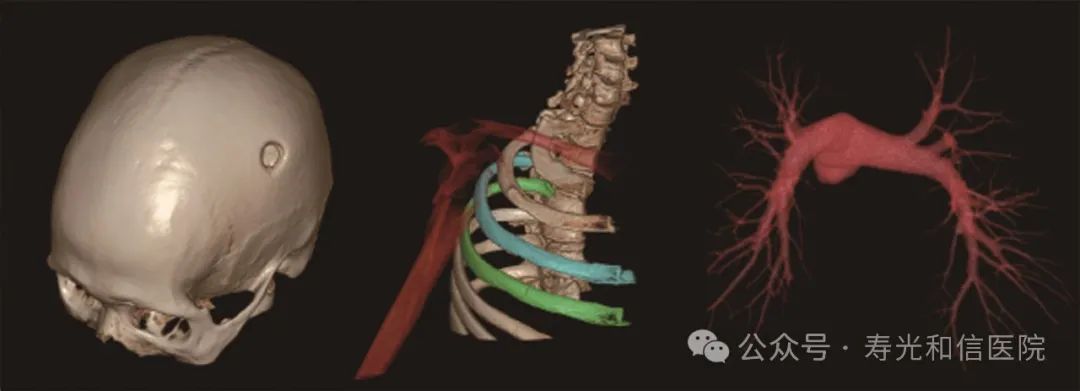

联影640层CT是中国CT届的“天花板”,集当今CT领域的顶尖科技于一身,将各项临床应用发挥到极致,为患者带来精准、舒适、安全的CT检查新体验。建立了心血管、神经、肿瘤、呼吸系统、泌尿系统及骨科专业等疾病的成像和低剂量筛查领域全新标准,真正实现全方位成像,结合AI人工智能技术,提高疾病诊断率。

联影640层CT采用宽体采集,一次检查即可获得全脑平扫图像、动静脉造影图像和灌注图像,不仅可应用于急诊缺血性脑卒中的影像评估,还可助力脑血管畸形、脑动脉瘤等其他脑血管病的结构和功能评估。

针对胸痛、脑出血、外伤、急腹症等多种急诊检查场景,联影640层CT提供全速急诊方案,检查时间最短化,图像评估直观化,为生命争分夺秒。